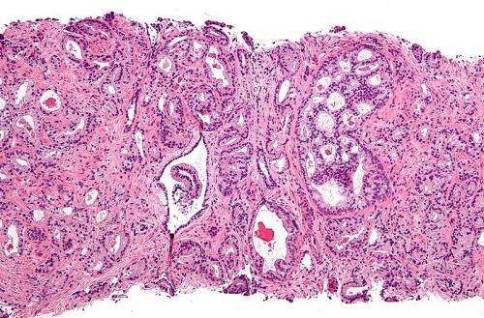

?圖片來(lái)自Wikipedia。

前列腺癌是指發(fā)生在前列腺的上皮性惡性腫瘤。2004年WHO《泌尿系統(tǒng)及男性生殖器官腫瘤病理學(xué)和遺傳學(xué)》中前列腺癌病理類型上包括腺癌(腺泡腺癌)、導(dǎo)管腺癌、尿路上皮癌、鱗狀細(xì)胞癌、腺鱗癌。前列腺腺癌在整個(gè)前列腺癌癥中占比較大,在95%左右,因此一般情況下人們所說(shuō)的前列腺癌就是代指前列腺腺癌。發(fā)病率隨年齡增長(zhǎng)而增加,具有明顯的地區(qū)差異。歐洲和美洲的發(fā)病率較高,亞洲較低。前列腺癌的發(fā)病率和死亡率僅次于肺癌,處于癌死亡的第二位。在大多數(shù)情況下,老年男性前列腺癌發(fā)展緩慢,不會(huì)導(dǎo)致死亡。